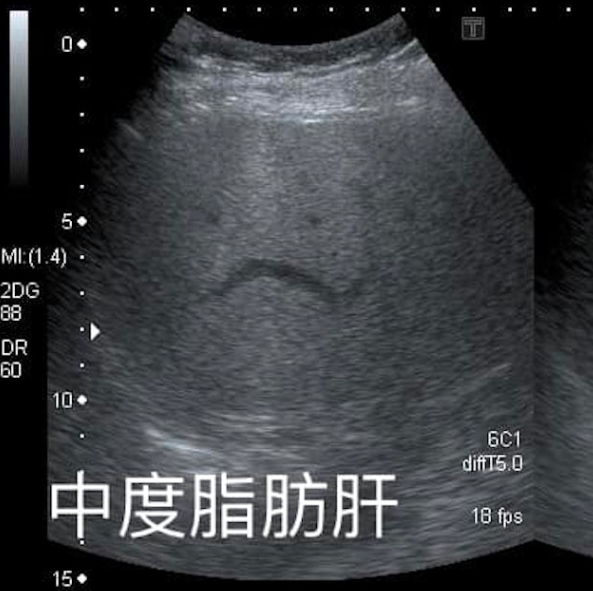

1名6旬妇去年仍患中度脂肪肝,但只靠「少吃水果」,短短1年就减重10公斤,连肝脏也恢复正常。从图片可见,肝脏有脂肪在B超下会显得颜色偏白。

患者是1名60多岁女士,患有长期高血压及脂肪肝,于去年检查时仍属于中度脂肪肝,体重为66公斤。但近日复诊B超时,医生发现她肝脏完全正常,脂肪消失了,更惊讶发现她在1年内成功减重约10公斤。